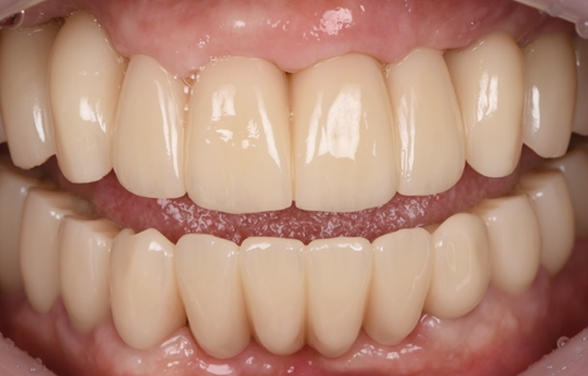

서울235치과 전체 임플란트는 페이셜 스캔, CT, 3D구강스캔

3가지 데이터를 기반으로 진단상담(모의치료 시뮬레이션)을 해

치료 전후를 미리 예상해볼 수 있고, 기능적/심미적 개선을

통해 드라마틱한 얼굴 변화를 얻을 수 있습니다.